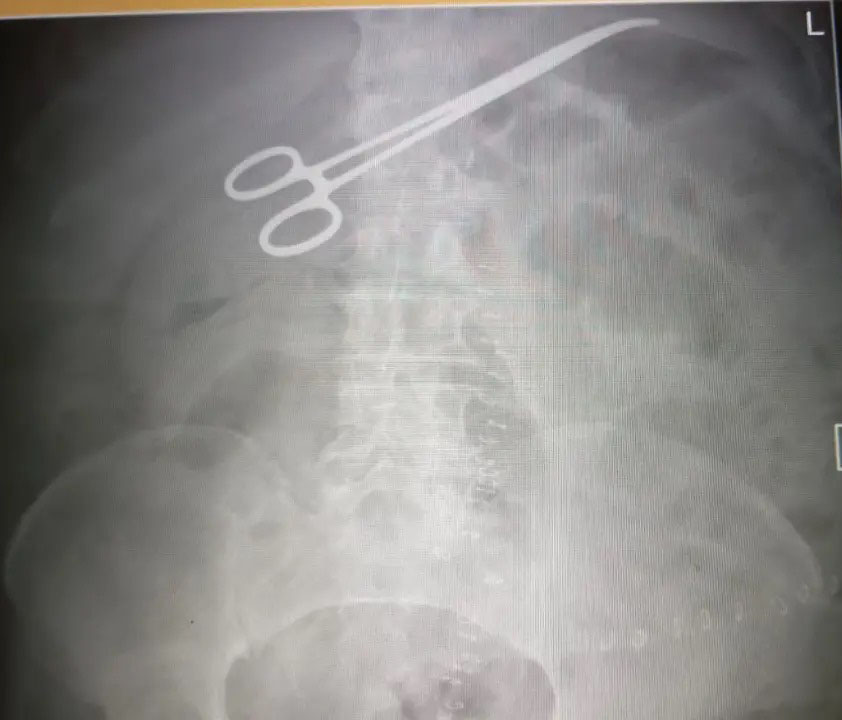

نسيان ملقط داخل بطن مريض بعد عملية بإحدى المستشفيات.. ما القصة؟

نشامى الاخباري _  أوضح مواطن، أن والده تعرض لمضاعفات خطيرة بعد عملية في الأمعاء بإحدى المستشفيات، حيث ظهر جسم غريب في صورة الأشعة، ما استدعى نقله إلى العناية المركزة.

ونفى مدير المستشفى، وجود “مقص عمليات”، مؤكداً أن الجسم كان ملقط عمليات، وأن العملية سارت بشكل طبيعي، والالتهاب مرتبط بحالة المريض الصحية.